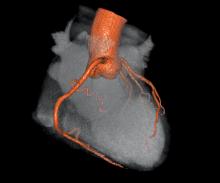

We are at an inflection point with many aspects of medicine, not the least of which concerns choosing the correct tool to discover and manage coronary artery disease. The American landscape of clinical and imaging service providers is going through a major reshuffle. Coronary computed tomography angiography (CTA) is growing in utilization, taking its place as an established modality with AHA-, ACC- and ACR society-derived appropriate use standards. However, this growth in CT utilization and the resultant growth in per capita radiation exposure have elevated a very public debate about the risk of causing cancer versus the value of its information content.